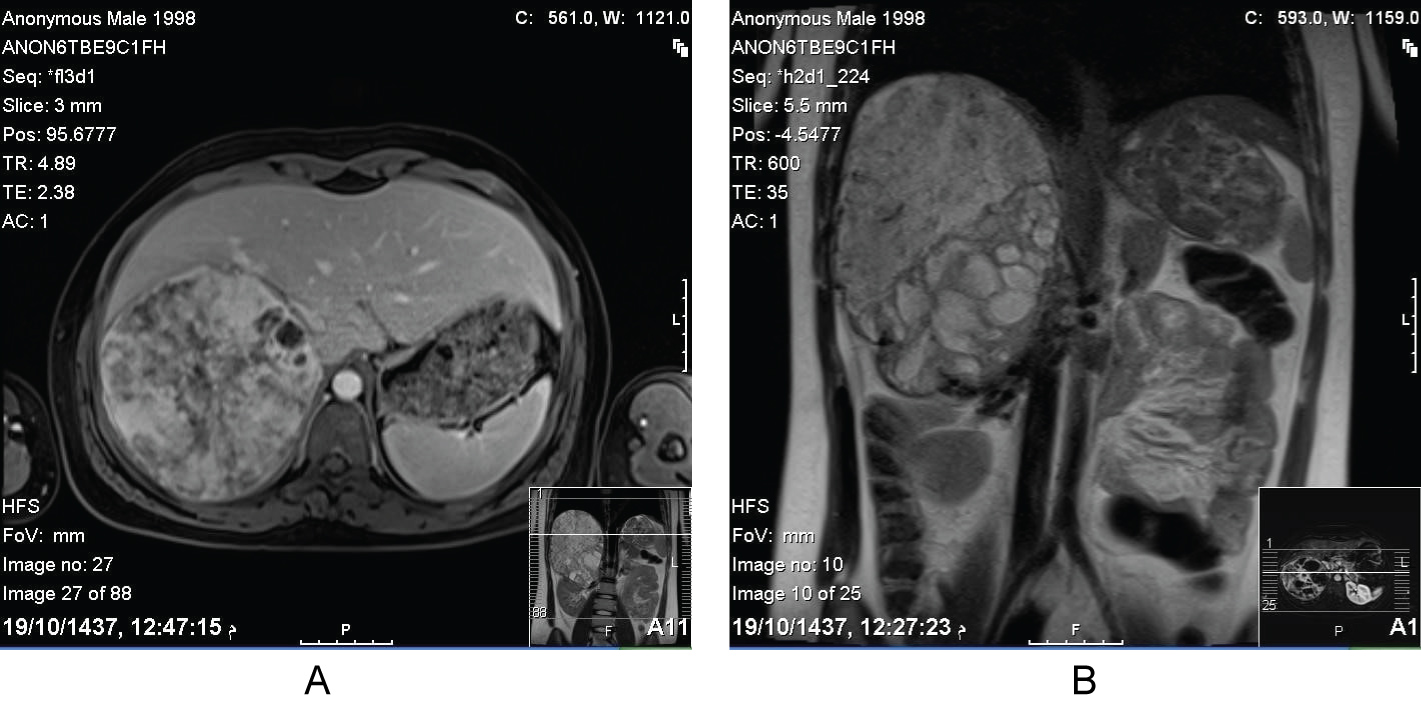

Open surgical approach was carried out. A 16 cm well-encapsulated mass was identified with dense adherence to the inferior vena cava and the posterior surface of the right liver. However, there was no evidence of gross invasion to the surrounding structure nor were there any obvious metastatic lesions. It was completely excised en-bloc with the right adrenal gland and the surrounding Gerota's fascia as well as the locoregional lymph nodes including the renal Hilary lymph nodes. The tumor capsule was not perforated and there was no need for vascular resection or frozen section biopsy. Blood pressure was monitored closely intra- and post-operatively without any incidence of increased blood pressure. The patient was released 5 days after surgery in good clinical condition.

(Figure 2a and Figure 2b).

Figure 2: Intraoperative images show the huge (16 cm) adrenal mass (long arrow), the Inferior Vena Cava (short arrow) and the right liver lobe (dotted arrow). View Figure 2